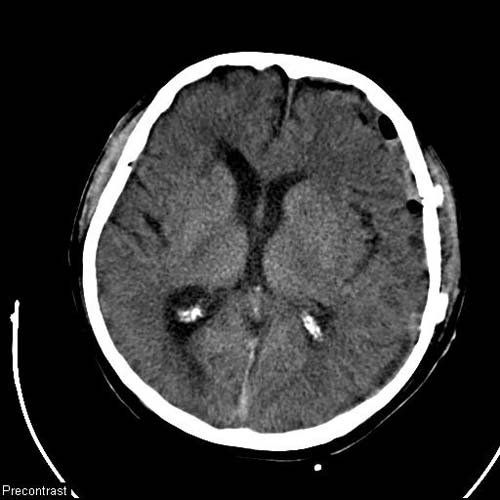

Radyolojik Görüntüler